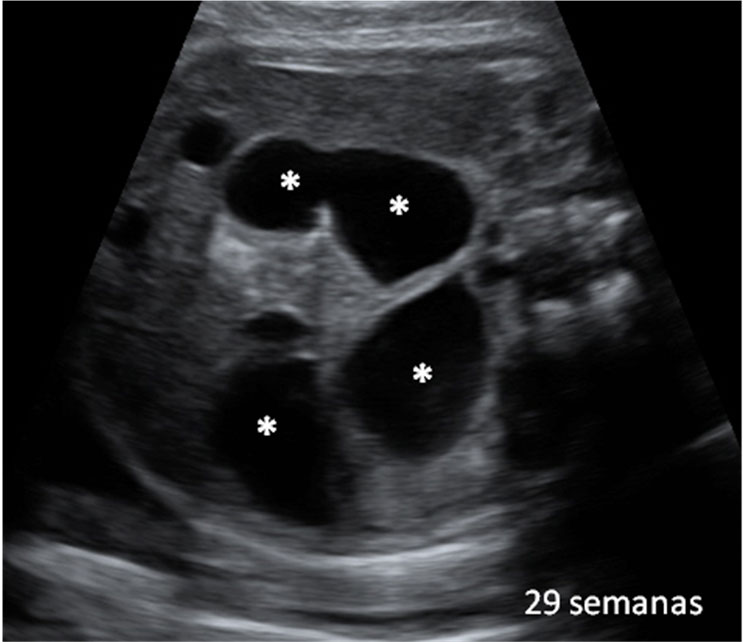

En la ecografía en 3D vemos a un bebé de 20 semanas de gestación se tapa la cara con ambos brazos y aprieta los puños. Se trata de un gesto innato que mantendrá en la cuna durante los primeros meses de vida.

Ecografía Embarazo 2D y 3D - SEMANA 20